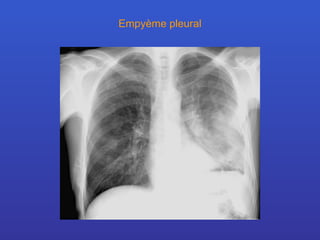

Empyème pleural